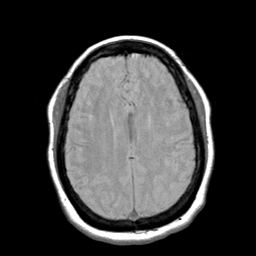

Cerebral hemorrhage, MR Study mr-pd -- Slice #16

[Home][Help][Clinical] Slice 16